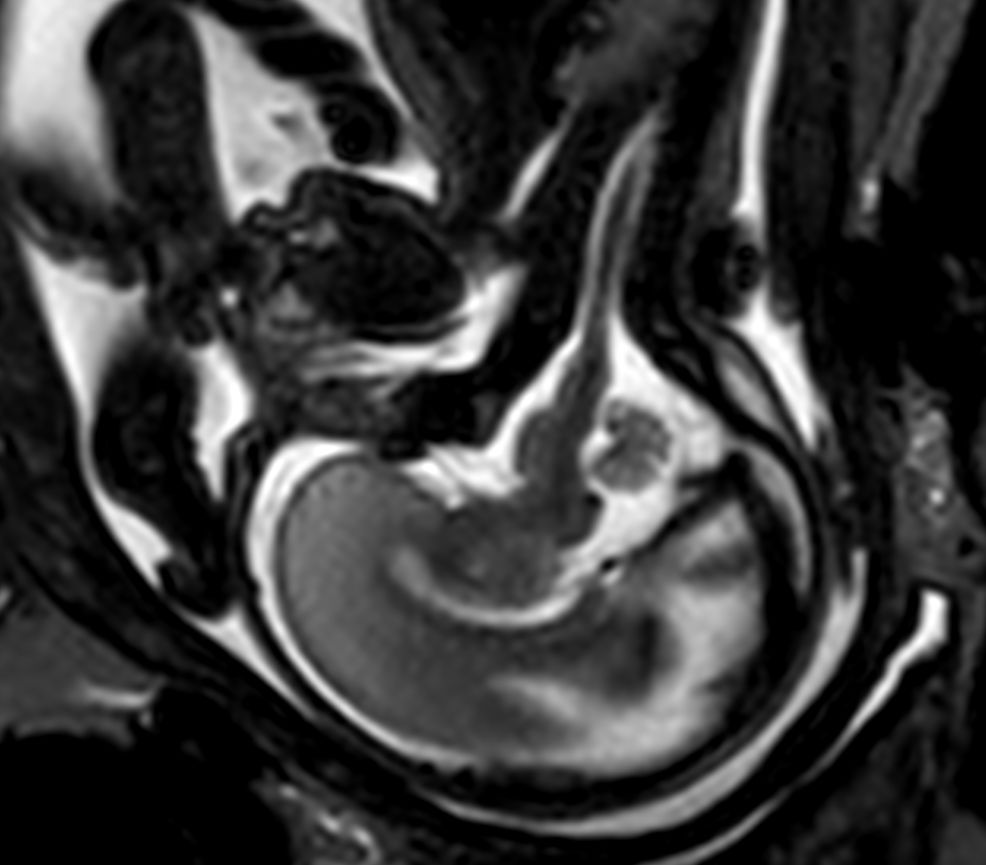

Pregnant patient, referred to MRI for fetal brain and spine imaging.

Sagittal T2w TSE single shotCompressed SENSE